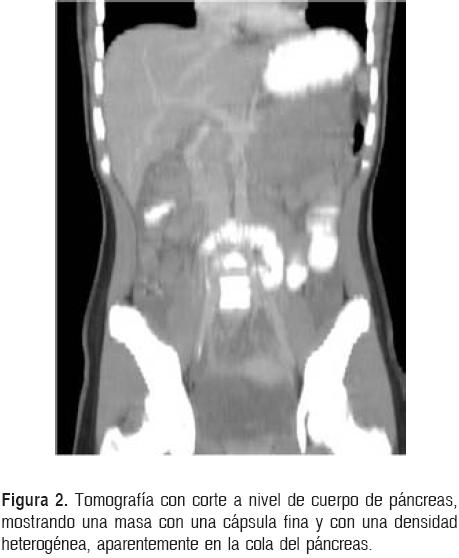

Los exámenes de laboratorio fueron normales, incluidos los niveles de α-feto-proteína y β-gonado-tropina coriónica humana. Se realizó ultrasonido que muestra lesión en cuadrante superior izquierdo, de 8 x 9 x 5 cm aproximadamente, sólido, de aspecto heterogéneo y cápsula bien definida (Fig. 1). Se realiza tomografía axial computarizada (TAC), en la que se observa un tumor de aproximadamente 8 x 8 cm, heterogéneo, bien definido por la presencia de una cápsula (Fig. 2). La imagen por resonancia magnética (IRM) de la lesión en sentido axial (Fig. 3) revela el tumor ocupando gran parte del cuadrante superior izquierdo.

Los estudios de imagenología para el diagnóstico de estas lesiones son: el ultrasonido, la tomografía axial computarizada (TAC) y la imagen por resonancia magnética (IRM). En las placas simples de abdomen pueden observarse estructuras desplazadas o calcificaciones.9 Por otra parte, en el ultrasonido se visualiza una masa con áreas de alta y baja ecogenicidad sin septos en su interior,34 y la angiografía demuestra zonas de poca vascularidad.9,38 En la TAC, los TSP se presentan como masas heterogéneas grandes con presencia de una cápsula.25 Las zonas de hemorragia tienen hiperatenuación y las áreas de degeneración quística se observan con hipoatenuación. Las calcificaciones se observan en el 30% de los casos. Con el contraste se observa un reforzamiento periférico heterogéneo con un centro de baja densidad.39 La cápsula suele ser hi-perdensa (70%) y los tumores pueden presentar un nivel líquido en su interior (10%).35 Las calcificaciones son raras, pero cuando existen, se encuentran en la periferia del tumor.40 Algunos autores han reportado una frecuencia de calcificaciones de aproximadamente 40%.23,31 En las resonancias magnéticas se muestra una heterogeneidad en 73.5% de los casos y en 89% son hiperintensas. La presencia de hemorragias dentro de la lesión se observa en más del 70% de los casos.35 Las áreas de hiperintensidad en la serie T1 y de hipointensidad baja o no-homogénea en la serie T2 ayudan a identificar las áreas de hemorragia y también ayudan a diferenciar los TSP de otros tumores pancreáticos.19 Las zonas sólidas en la serie T1 se muestran hipointensas, aunque pueden verse ocasionalmente zonas de hiperintensidad.41 Se ha sugerido realizar biopsias por punción por aspiración con aguja fina (PAAF) percutánea guiada por TAC, aunque no se ha difundido su uso debido a complicaciones potencialmente serias.37 Por ello, se ha sugerido la posibilidad de realizar biopsias por aspiración con aguja fina guiada por ultrasonido endoscópico, ya que muestran sensibilidad de 81.6% y especificidad de 87.5% para tumores no neuroendocrinos.42 Las complicaciones con este método diagnóstico apenas son del 2%.43 El TSP también se ha detectado con la tomografía por emisión de positrones; se puede observar una captura elevada de la F-18 fluorodeoxiglucosa por la lesión.44